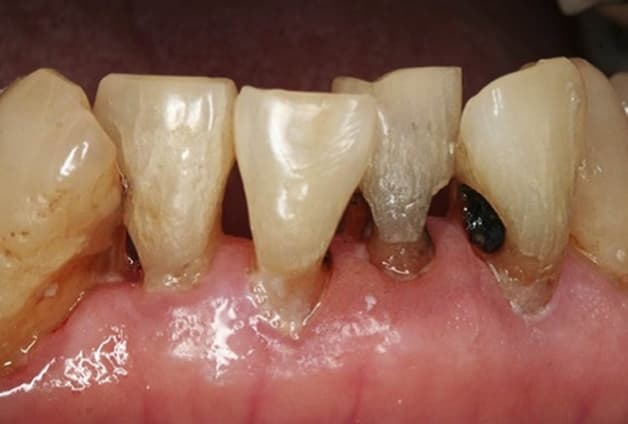

Sâu răng dưới nướu chính là tình trạng khi chân răng bị sâu

Sâu răng dưới nướu là tình trạng khi phần chân răng bị sâu. Nguyên nhân là do vi khuẩn tấn công, phá hủy phần cấu trúc của răng. Điều này sẽ khiến người bệnh gặp khó khăn khi ăn uống. Bên cạnh đó, hệ tiêu hóa của người bệnh cũng sẽ bị ảnh hưởng tiêu cực. Lý do là răng bị sâu không đủ lực để nghiền nát thức ăn. Tình trạng này nếu kéo dài, không được khắc phục sẽ dẫn tới nhiều biến chứng nguy hiểm. Ví dụ như những biến chứng về mất răng vĩnh viễn, áp xe chân răng, viêm xương hàm. Nguy hiểm hơn, bệnh nhân có thể bị ung thư vòm họng.

Tình trạng sâu răng ở dưới nướu có thể kéo dài với nhiều biểu hiện. Những biểu hiện tiêu cực xảy ra như tụt lợi một phần, tụt lợi toàn phần, … Từ đó, vi khuẩn gây hại sẽ được tạo điều kiện phát triển, ảnh hưởng xấu tới sức khỏe răng miệng. Đồng thời, tình trạng này nếu không sớm điều trị sẽ ảnh hưởng tới cả sức khỏe toàn thân.